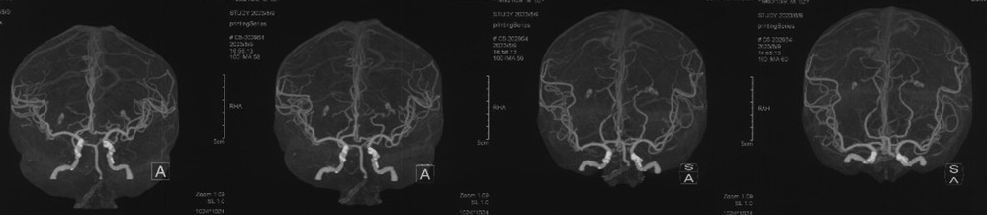

手术预案

• 病例特点:右侧颈内动脉C1段重度狭窄,致远端供血区域脑梗死,手术指征明确;

• 拟局麻下行右侧颈内动脉血管成形术;

• 患者因胸憋、心悸入住我院心内科,于我院心内科行冠脉支架植入术。本次转入我科后,不到一周,行颈内动脉球囊扩张术及支架植入术。考虑患者非极重度狭窄,预先通过Wallstent支架后扩可行,后扩支架贴壁性更好。考虑到患者虽无明显神经系统症状,但在核磁上却有颈内动脉狭窄侧的多发梗死病灶,发病机制动脉到动脉栓塞可能性大,故选用网眼最小,同时通过性最好的Filterwire保护伞Wallstent闭环支架,预防栓塞事件。

手术过程

在路图指引下将Filterwire保护装小心通过狭窄段,送入右侧颈内动脉岩段释放,顺保护装置微导丝将Wallstent 9.0*40mm支架于狭窄段,准确对位后于病变处释放。

波科支架怎么样径技-弓上病例大赏|第210期·右侧颈内动脉球囊扩张术+支架植入术_https://www.jmylbn.com_新闻资讯_第17张

波科支架怎么样径技-弓上病例大赏|第210期·右侧颈内动脉球囊扩张术+支架植入术_https://www.jmylbn.com_新闻资讯_第18张

顺保护装置微导丝将LitePAC5.0*30mm球囊小心通过狭窄段,准确对位后以10atm压力扩张球囊。

波科支架怎么样径技-弓上病例大赏|第210期·右侧颈内动脉球囊扩张术+支架植入术_https://www.jmylbn.com_新闻资讯_第19张

波科支架怎么样径技-弓上病例大赏|第210期·右侧颈内动脉球囊扩张术+支架植入术_https://www.jmylbn.com_新闻资讯_第20张

撤回保护装置及导引导管,封堵器封堵血管鞘,自然中和肝素,术后患者病情平稳,安全返回神经内科病房。